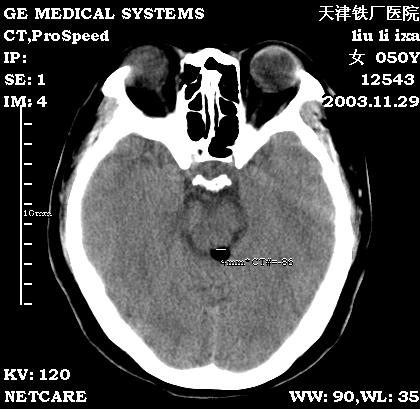

四叠体池脂肪瘤

患者:女,患者头部不适,前来就诊。

zzzsssjjj发言:考虑四叠体池脂肪瘤,该病1856年由rokitansky首先报道,此病属先天性病变,属神经管闭合异常畸形,常见于胼胝体,也可发生四叠体池、鞍上池等,其边缘也可钙化。

1、部位:四叠体池,为脂肪瘤的好发部位

2、常合并其他部位的先天畸形。

3、鉴别诊断:于畸胎瘤和皮样囊肿鉴别

结果:患者在天津环湖医院行mri检查也考虑:脂肪瘤